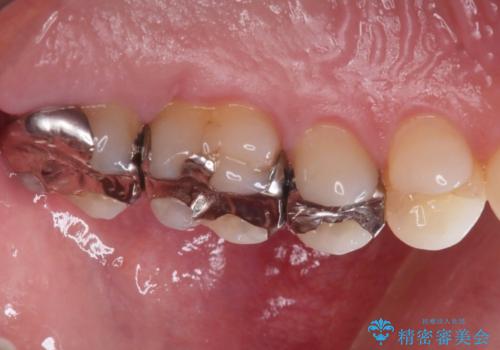

最新の症例

Latest cases